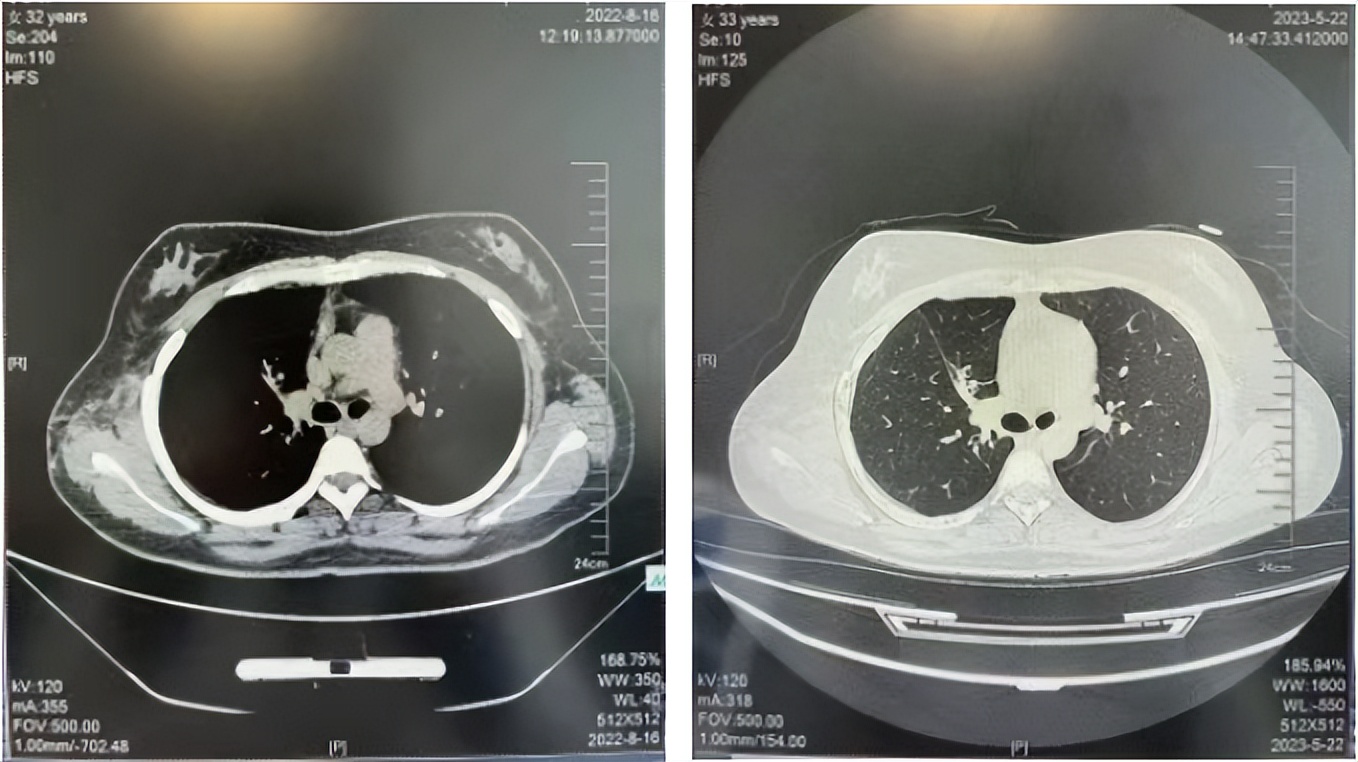

2016年1月复查CT提示支气管截断可见新发小结节,一线治疗采用培美曲塞+DDP方案化疗4周期(培美曲塞3.36,DDP 480mg)。化疗后复查胸部CT:右肺见不规则结节样影,最大层面大小约19mm*8mm,较前比较明显增大,疗效评估PD。2017.3-2017.4予单药多西他赛化疗3周期,疗效评估SD。2018年5月末复查CT提示结节较前增大,评效为PD,2018年6-10月予多西他赛+CBP化疗4周期,疗效评估SD。2022年5月患者出现活动后气短,复查胸部CT示右肺膨胀不良;右侧胸腔积液增多。胸腔积液包埋病理示符合肺腺癌细胞。行NGS基因检测:EML4:exon13-ALK:exon20融合。PD-L1(克隆号22C3)TPS<1%。

临床诊断:右肺上叶恶性肿瘤rT0N0M1a IVA期(第9版分期);恶性胸腔积液。

诊疗经过:2022年5月始口服克唑替尼3个月,出现肝功能异常(DILI 2级伴临床症状),改用恩沙替尼靶向治疗至今,目前评效为维持PR。恩沙替尼应用期间出现轻度肝功能异常(DILI 1级),对症处理后好转。截止目前PFS 33个月。

2018.07

2022.05

2022.08

2023.05